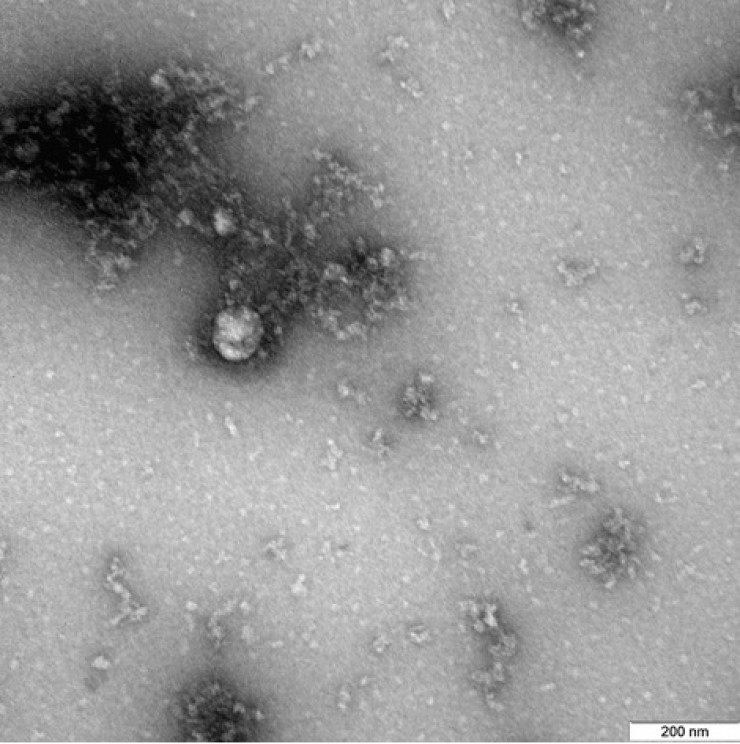

Роспотребнадзор ғалымдары алғаш рет коронавирустың "ұлыбританиялық" штамын микроскоппен суретке түсірді. Ведомство сайты "ұлыбританиялық" коронавирустың жаңа түрі пациенттен 2020 жылдың желтоқсанында алынғанын мәлімдеді, - деп хабарлайды Tengrinews.kz тілшісі.

"Вирустың микроскоппен түсірілген фотосуреті жаңа коронавирус нұсқасының қасиеттерін, құрылымдық ерекшеліктері мен зертханалық жануарларды қолдана отырып, жасушалық дақылдар мен эксперименттік модельдердегі көріністерін зерттеу аясында алынды", - делінген хабарламада.